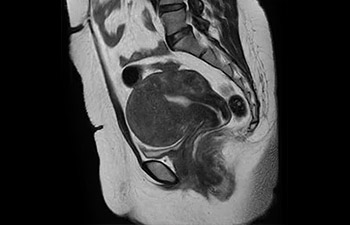

Pelvis

Pelvis de mujer con mioma

con Compressed SENSE